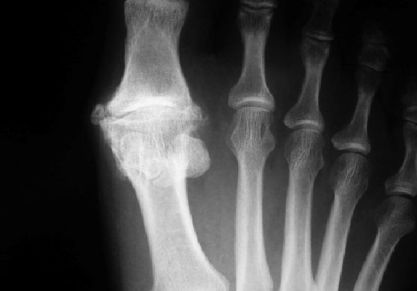

• Подагра. Это хроническая патология, характеризующаяся повышенным количеством мочевой кислоты в крови. Далее, она превращается в соль и откладывается в суставах. Именно она вызывает воспаление суставов.